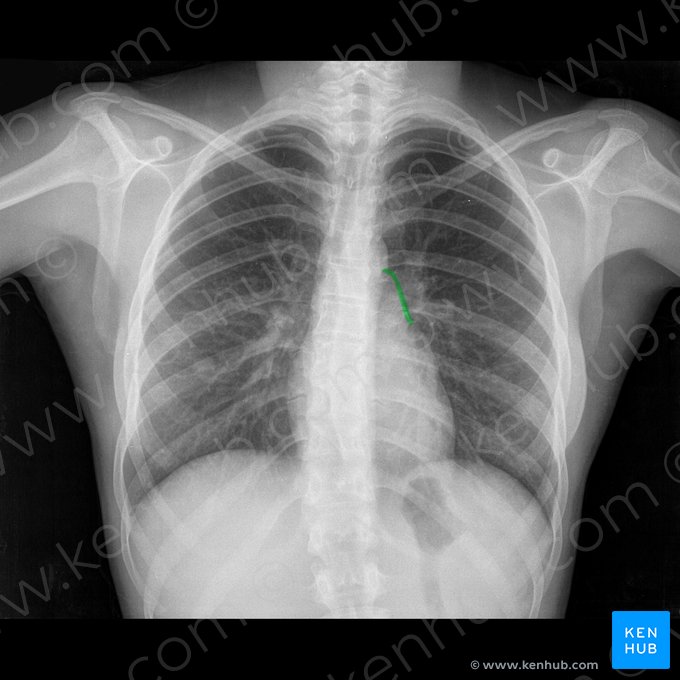

Eine Röntgenaufnahme des Brustkorbs (auch Röntgen-Thorax genannt) ist ein häufig genutztes bildgebendes Verfahren. Es kann aus verschiedenen Perspektiven aufgenommen werden: postero-anteriore Projektion (p.a.), antero-posteriore Projektion (a.p.), linke und rechte laterale Projektion (l.l., r.l.). P.a. und a.p. werden am häufigsten verwendet, während seitliche Projektionen zur Befundung der Wirbelsäule genutzt werden und um zu beurteilen, wie nah sich eine Struktur an der Brustwand befindet. Bei der Überprüfung eines Röntgenbildes müssen wir zunächst die Bildqualität mit folgendem Schema bestimmen: Rotation (Schlüsselbeine und Wirbelsäule in gleichem Abstand), Inspiration (mindestens 9 Rippenpaare sollten zu sehen sein), Projektion (handelt es sich um eine a.p-, p,a,-, l.l- oder r.l.-Aufnahme) und Belichtung (Lungenspitzen, Rippenwinkel und Brustwirbel sollten alle zu sehen sein).

Dann können wir zur Beurteilung des Bildes übergehen. Am einfachsten lässt sich eine Röntgenaufnahme des Brustkorbs nach der ABCDE-Regel auswerten, die für Airway (Atemwege), Breathing (Beatmung), Cardiac (Herz), Diaphragm (Zwerchfell) und Everything else (alles andere wie Knochen, Weichteile, Brust) steht.

Wenden wir nun diese Techniken an, um die folgenden Röntgenbilder des Thorax auszuwerten und das normale anatomische Erscheinungsbild des Brustkorbs zu beurteilen.